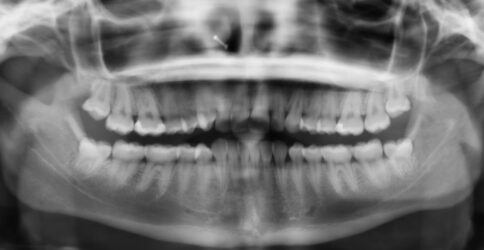

I have a case share. I have a patient who presented with Pericoronitis tooth number #1 and other impacted wisdom teeth. Medical history significant for von Willebrand‘s disease. I had a difficult time getting a medical status update from her PCP. Upon questioning the patient, it looks like a bleeding issues haven’t been too severe for her. However, I was concerned because my treatment plan included the removal of all four impacted wisdom teeth.

In this case, I modified my prescribing regiment to include 650 mg of transexamic acid in addition to analgesic medication. (Sig: instructed to take three times a day for up to four days.)

I had the patient take her first dose of transexamic acid with her oral sedatives one hour pre-op.

I was pleasantly surprised to observe the bleeding control we achieved immediately postop surgery referenced in the photos.